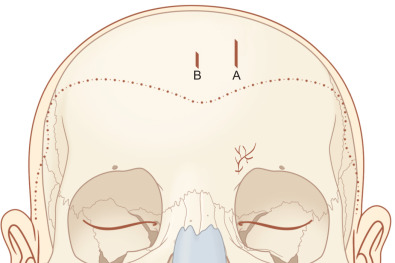

The coronal incision is marked out at least 4–6 cm behind the hairline. The hair can be banded and need not be shaved. The incision may be a peaked line ( Fig. 1.7.13 ) or “zig-zag” ( Fig. 1.7.14 ). The zig-zag incision assists with scar camouflage; taking advantage of the hair’s inferior alignment which covers the transverse arms of the scar. The scalp is opened in thirds to minimize blood loss. Hemostasis during the initial scalp incision is addressed with limited use of bipolar cautery (minimizing damage to hair follicles), local sutures, or hemostatic clips according to surgeon preference.